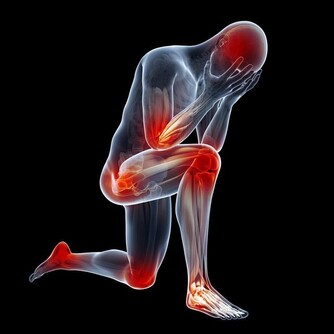

維生素D缺乏症狀包括疲倦、肌肉無力和脫髮。如果發現自己也有這些症狀,很可能缺乏維生素D,你可以通過多補充些富含維生素D的食物或者多曬曬太陽來改善這一症狀。

如果你出現持續背痛或者經常感覺不舒服,以及經常感覺疲倦,你也可能面臨維生素D缺乏的風險。蛀牙、脫髮或慢性肌肉疼痛也可能是維生素D缺乏的警示信號。經常頭痛的人也有維生素D缺乏的風險,這一症狀常常被人們所忽略。